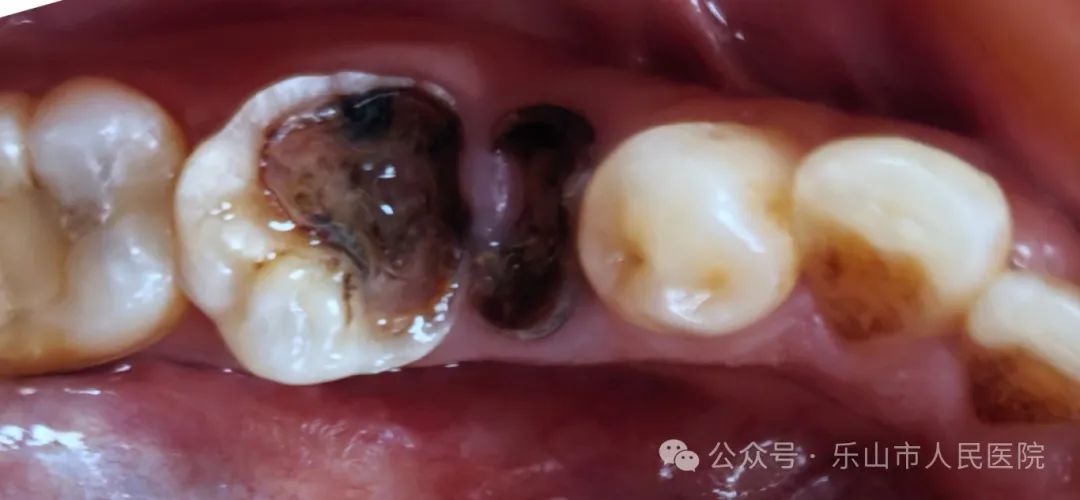

牙齿发黑、有洞,怎么办?

牙齿出现了小黑洞,但是没有感觉到疼痛,要紧吗?是不是能不管它呢?本期带你一起来了解龋病。

龋病是大家口腔里最常见的一种疾病,俗称蛀牙、虫牙。是一种以细菌为主的多种因素作用下,造成牙体硬组织无机物脱矿、有机物分解,导致牙齿产生色、形、质改变的一种感染性疾病,是不可逆的。也是造成牙痛的主要原因之一。

轻者变色引起缺损,重者可引发牙髓病及根尖周病等更严重的疾病,造成牙齿疼痛加剧,甚至引发颌骨骨髓炎等并发症。未经治疗的龋齿还有可能成为口腔病灶,影响局部乃至全身健康。龋病是造成牙齿丧失的主要原因。儿童牙齿如果早期丧失,不仅妨碍消化功能,还会影响颌面部的正常发育,导致牙齿生长发育问题及牙列不齐。